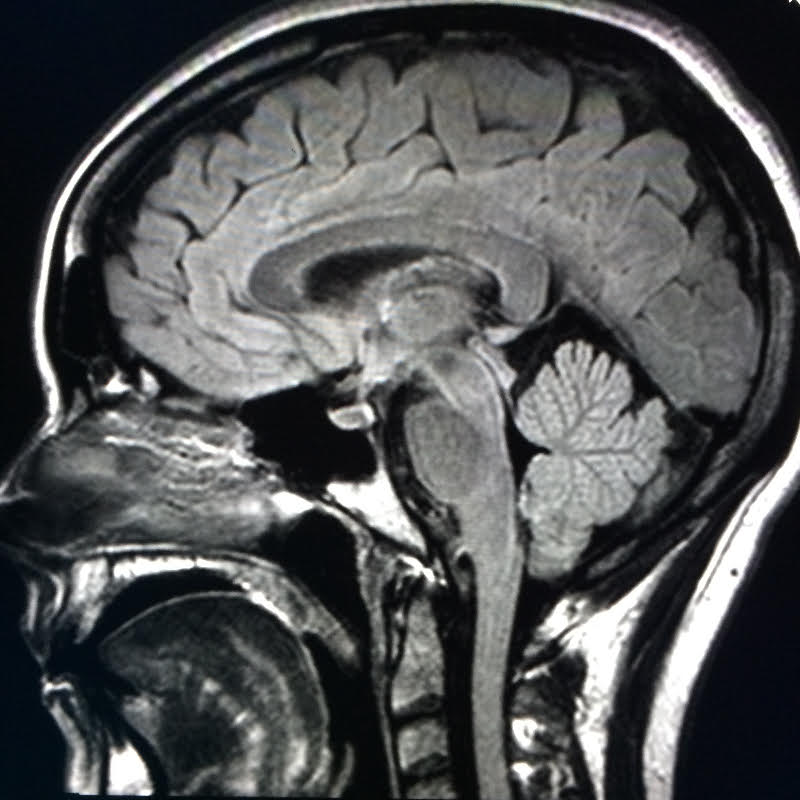

Residency in diagnostic radiology is four years, generally preceded by an internship year in medicine or surgery. Specialization has become the norm, with most fellowships lasting one year thereafter. In medical school we learn anatomy by rote memorization. Radiologists must master imaging anatomy – the way organs and disease appear on x-ray, computed tomography, ultrasound and magnetic resonance imaging. As a Neuroradiologist, I triangulate lesions in the brain by carefully scrutinizing MR imaging in three orthogonal planes. Developing a heightened spatial orientation takes time, discipline and commitment. Invoking Malcom Gladwell’s “10,000 hour rule”, the beginner radiologist, like the novice tennis player, has to work tirelessly. To become good at anything requires practice, lots of it.